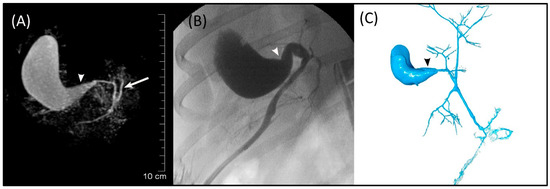

The GB (fundus, body, and neck), cystic duct, and CBD (at papilla and at extrahepatic ducts’ junction) were visible in MRCP, FRCP, and corrosion casting in all eight dogs. Visual comparisons between MRCP, FRCP and corrosion casting in Dog 6 with no evidence of disorders and Dog 8 with biliary disorders are shown in Figure 2 and Figure 3, respectively. The extrahepatic ducts and pancreatic ducts were variably visible in the MRCP and FRCP images. This did not allow for statistical analysis, only descriptive assessment.

The diameter of the extrahepatic ducts, GB (fundus, body, and neck), cystic duct, CBD (at papilla and at extrahepatic ducts’ junction), and pancreatic ducts of Dog 8 are presented in Table 4.

The maximum diameters of the CBD at papilla and extrahepatic ducts’ junction measured by MRCP in the seven dogs without disorders of the biliary tract were 2.27 and 3.50 mm, respectively. Measurement of the CBD has been used to evaluate obstruction of the biliary system. The mean diameter of a normal CBD at its distal part as measured by ultrasonography has been proposed to be <3 mm [34]. However, that study was performed in only three dogs weighing 14 to 20 kg. Therefore, a 3 mm cut-off value may not be a clear and reliable criterion across various dog breeds and body weights. The CBD diameter in seven healthy beagle dogs with a mean body weight of 14.1 ± 3 kg was earlier measured in ERCP with a measurement of 3.04 ± 1.89 mm at the duodenal papilla [16]. Recently, the CBD diameter at the porta hepatis, duodenal papilla level, and mid-portion was assessed using computed tomography in 283 healthy dogs weighing 1.5 to 29.5 kg [35]. The age of the dogs in that study varied between 0.5 and 17 years (mean 8.8 years). No correlation was found between CBD diameter and dog age, but there was a significant difference in the CBD diameter at each measurement point between body weight groups [35]. Furthermore, the body weight and CBD diameter showed a positive linear correlation at each point. Thus, the normal reference ranges of CBD diameter should be applied for different body weights. The discrepancy between the diameter measurements of the CBD obtained in our study and the previously reported measurements is likely due to the fact that the measurements were performed by different imaging modalities in dogs with varying body weights. Even though age of the dog has not been found to be related to the CBD diameter [35], the effect of old age on the measurements remains unknown. The youngest dog in our study was 9 years old. Dog 8 with cholangitis and cholestasis exhibited a dilated GB neck in MRCP, FRCP, and corrosion casting when compared with the seven dogs without disorders of the biliary tract. In a study of 45 dogs with cholangitis confirmed by histopathology, ultrasonography showed a distended GB in 24 dogs (53.3%) [1]. In a retrospective study, ultrasonography revealed distended GB in three of seven dogs with various types of cholangitis; one out of those three dogs had concurrent biliary stasis [17].

Figure 3. Images of Dog 8 with acute extrahepatic cholestasis and focal destructive cholangitis. (A) 3D-TSE-MRCP illustrating dilated gallbladder neck (arrowhead). Normal left extrahepatic duct is visible (arrow). (B) FRCP image showing dilated gallbladder neck (arrowhead). (C) Corrosion cast demonstrating dilated gallbladder neck (arrowhead).